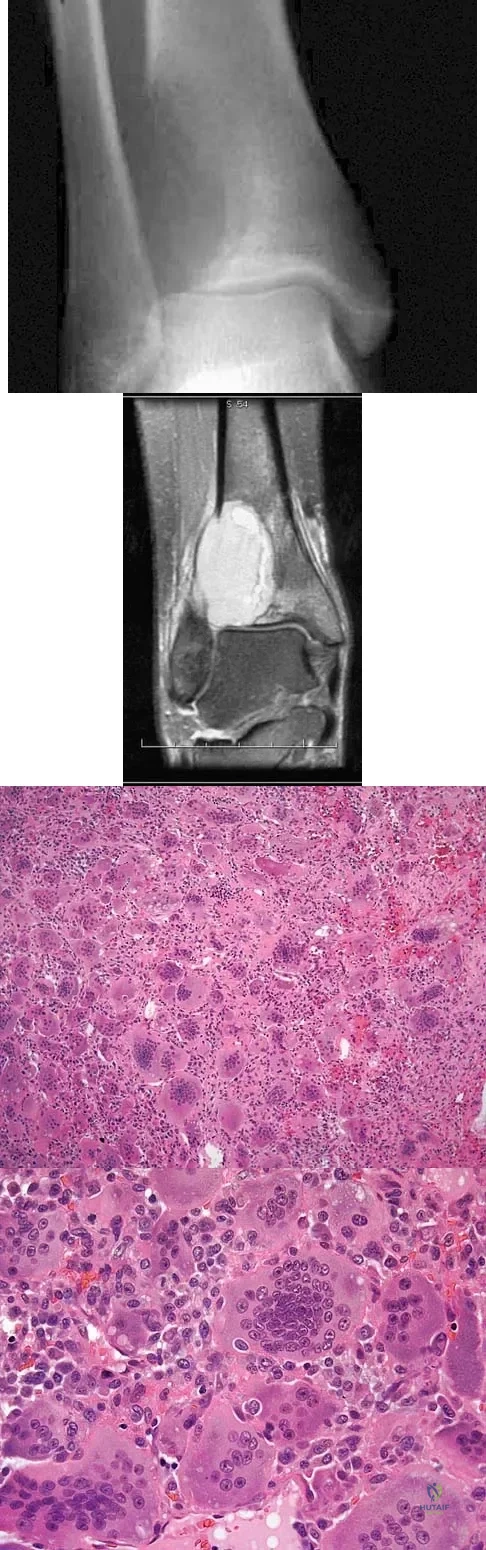

A 13-year-old patient has foot drop and lateral knee pain. AP and lateral radiographs and an MRI scan are shown in Figures 49a through 49c. A biopsy specimen is shown in Figure 49d. What is the preferred method of treatment?